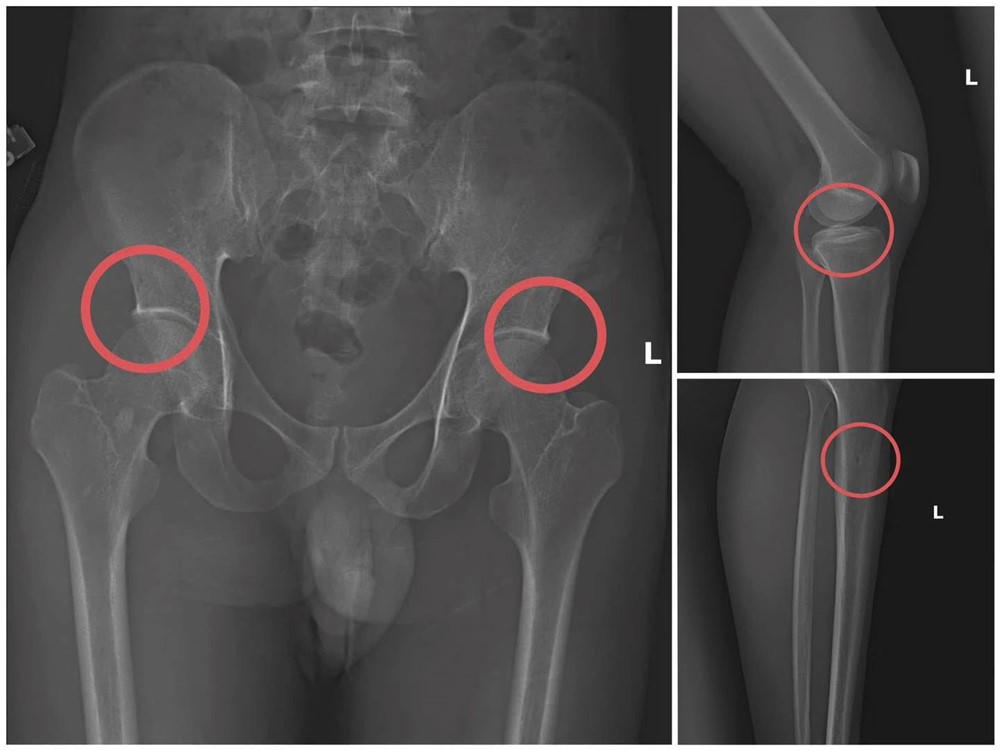

Theo điều tra, Châu vận động nhiều người mua bảo hiểm nhân thọ rồi tổ chức gây thương tích để tạo hồ sơ bệnh án giả. Châu trực tiếp tiêm thuốc mê cho các “khách hàng”, sau đó dùng kim tiêm, búa, đinh tác động vào vùng xương nhằm tạo vết nứt, vỡ tương tự chấn thương do tai nạn. Sau khi gây thương tích, các đối tượng được hướng dẫn dựng hiện trường giả như điện giật ngã, trượt chân xuống suối… để hợp thức hóa quá trình điều trị và hoàn thiện hồ sơ yêu cầu chi trả.

Vết nứt trong xương sau khi bị tác động